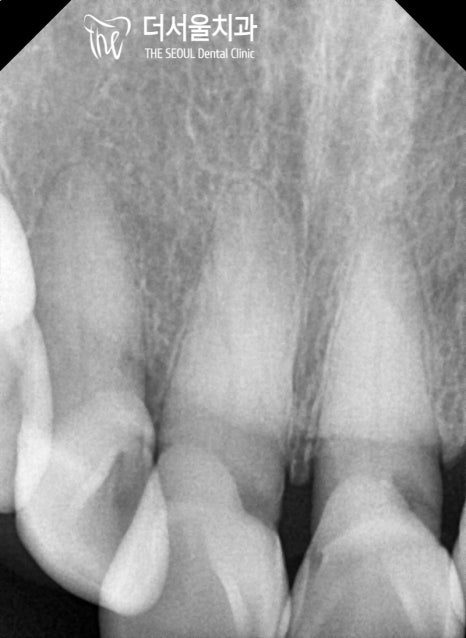

초진 구강 사진을 보면

곳곳에 생긴 우식과 치경부 마모증이

나타나 있는 것을 볼 수 있는데요.

눈에 잘 띄지 않는 곳까지 꼼꼼하게

살펴보는 것이 중요하기 때문에

치근단 방사선을 촬영하여 살펴본 결과

노인에게서 잘 발생하는 치근우식이

나타나 있는 것으로 확인되었습니다.

앞니 주변으로 치근 우식이 생긴 것으로 판단되어

# 11 # 21 엔도 코어 크라운,

# 12 레진 치료